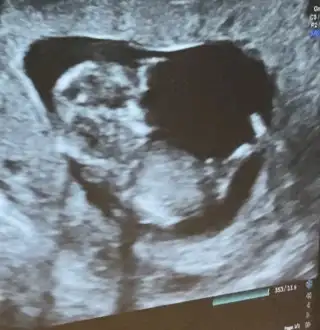

Yani 12 haftalıkken böyleydiUltrason resmin nasıldı senin, son hali![]()

Herkes öyle diyo ama ne biliyim ben bilerek kendimi erkeğe hazırladım şimdiden tekrardan değişmesin diyeKendimden gerçekten umudum yok çok çok barizdi ama senin değişebilir gibiydi ondan diyorum baya inceledim internette ondan diyorum![]()

ne bilim anlamadım açıkcası pek bişey :) inşallah gönlündeki olur sağlıklaYani 12 haftalıkken böyleydi![]()

Aynen çok küçük herşey değişebilirne bilim anlamadım açıkcası pek bişey :) inşallah gönlündeki olur sağlıkla![]()